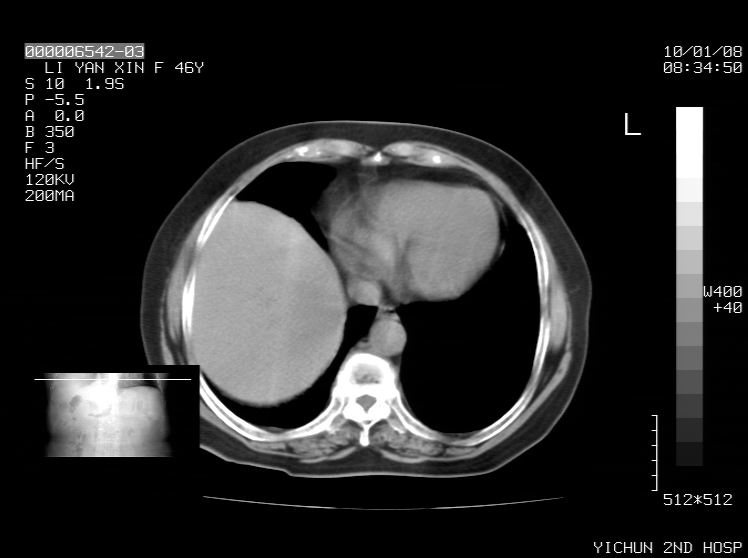

右侧膈膨升,胆囊壁厚,右侧肾脏缺如。病史?

右侧膈膨升,右肾脏切除术后

右侧膈膨升,肝内钙化灶,胆囊壁厚,右侧肾脏缺如。病史?

右膈膨出,肝脏变异,肝内钙化,右肾缺如,脾大。

右侧膈膨升,肝内胆管结石?

右侧肾脏缺如。病史?

右侧膈膨升,胆囊壁厚,右侧肾脏缺如,增强,腔静脉旁是否是移位肾

肝脏变异致膈升高,肝左叶肝内胆管结石.右肾萎缩,左肾代偿肥大.

胆囊ct未见确切异常,请结合b超。右侧肾窝未见确切肾脏影,右肾萎缩?异位?

右侧膈膨升,肝内钙化灶,胆囊壁厚,右肾萎缩或发育不良。